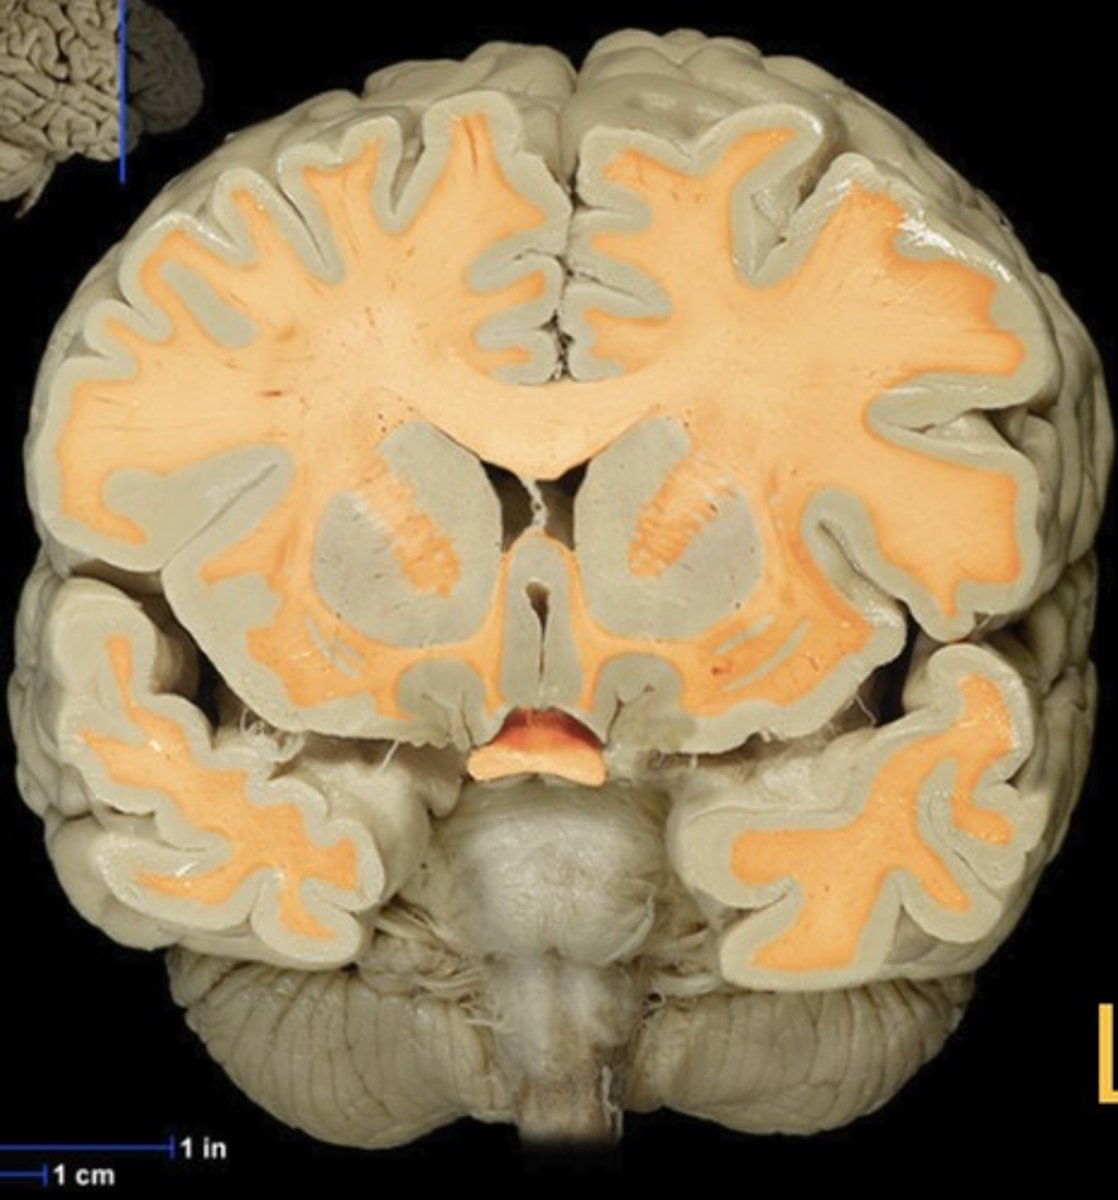

White matter

Name this structure

White matter (anterior view of coronal section)

Name this structure

Corpus callosum

Name this structure

Globus Pallidus

Name this structure

Hippocampus

Name this structure

Hypothalamus (anterior view of coronal section)

Name this structure

Putamen

Name this structure

Thalamus (anterior view of coronal section)

Name this structure

Third Ventricle (anterior view of coronal section)

Name this structure